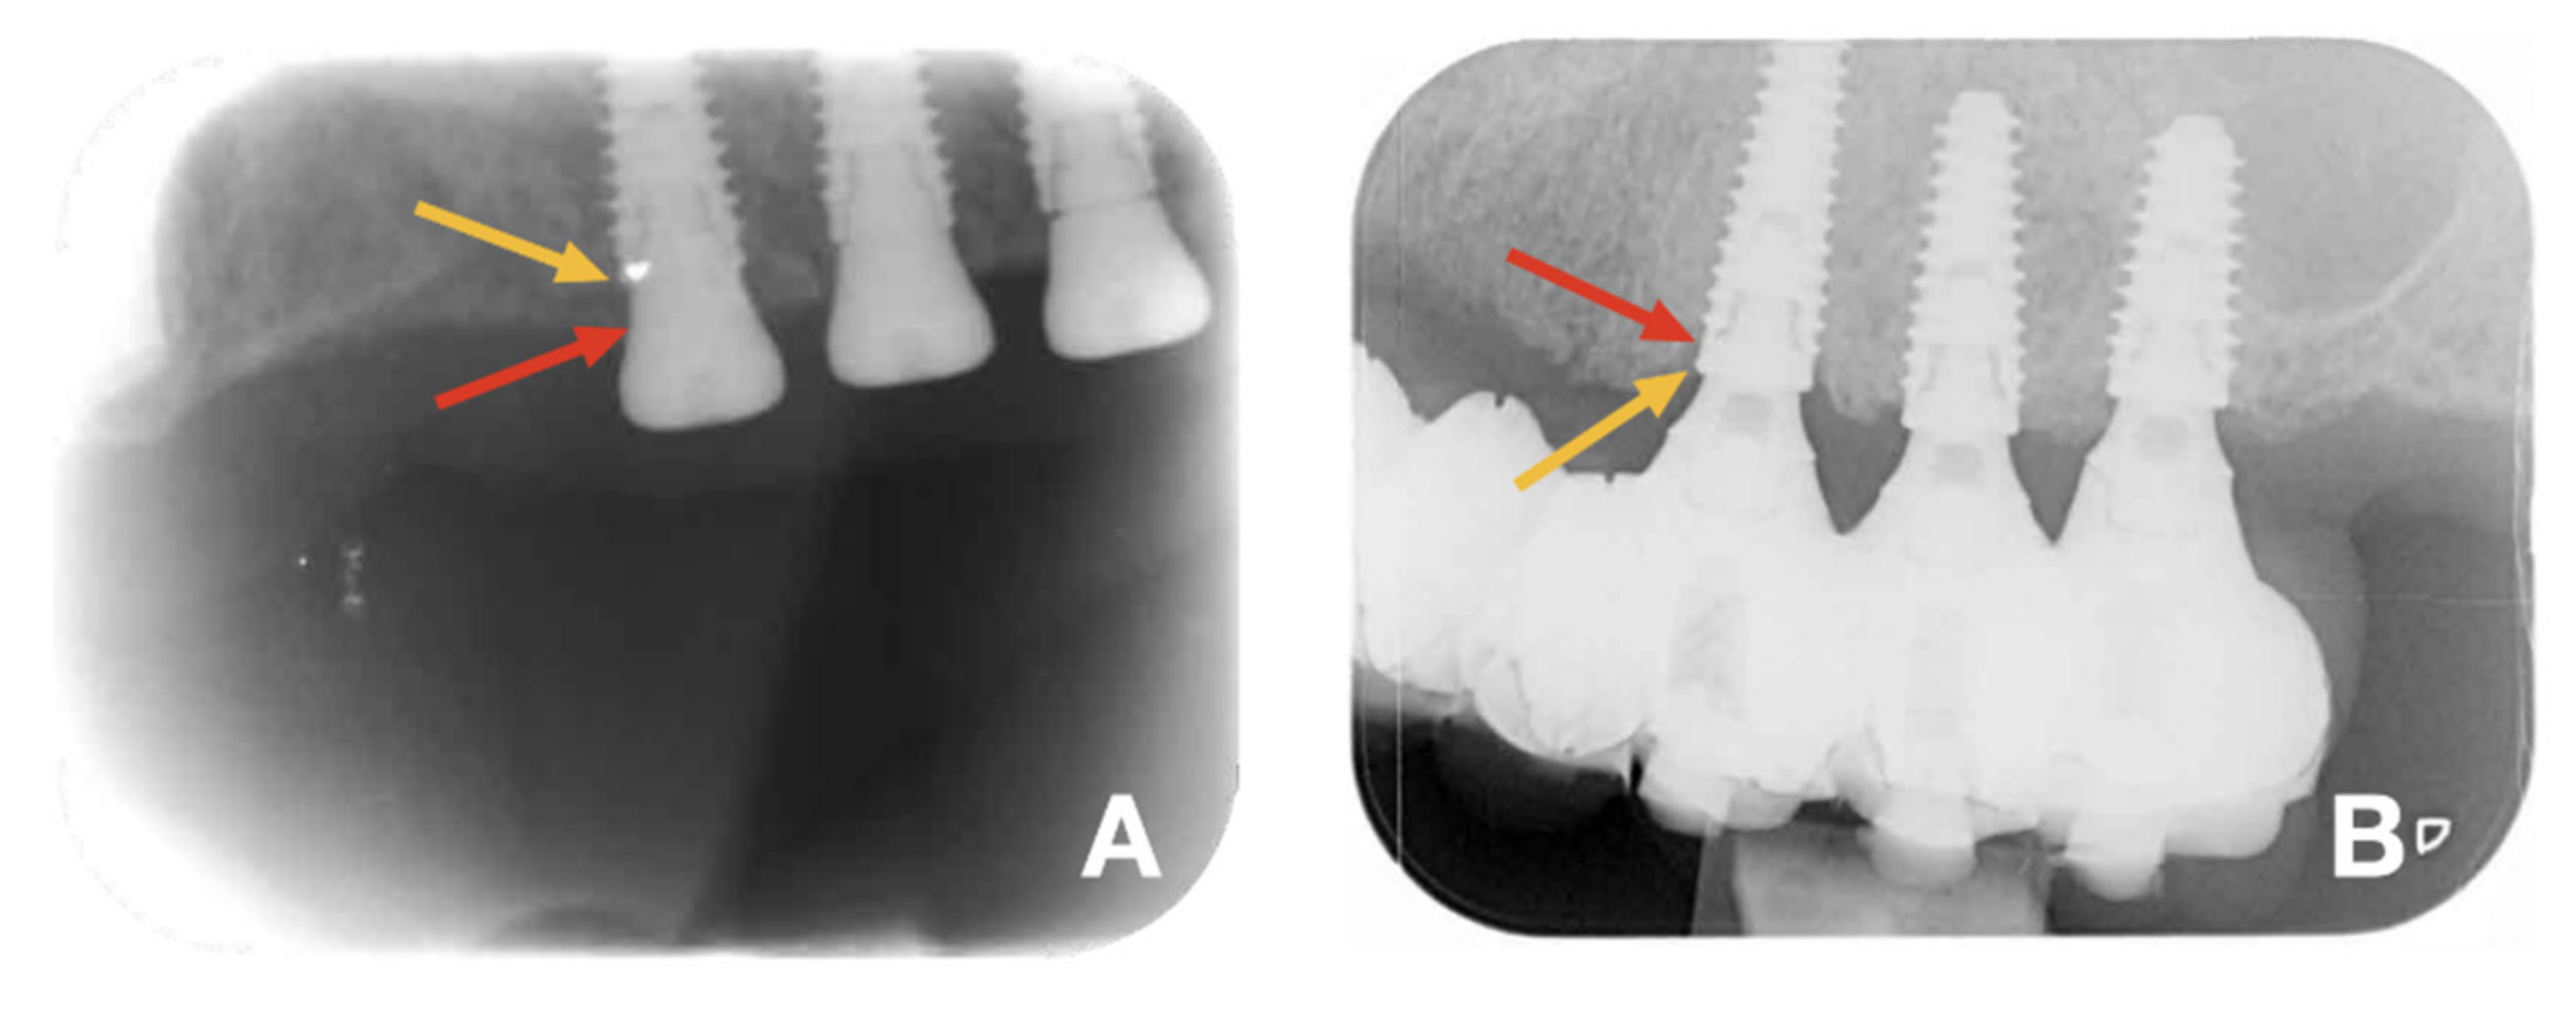

3.2. Bone Level and Probing Pocket Depth

4.2. Bone Loss